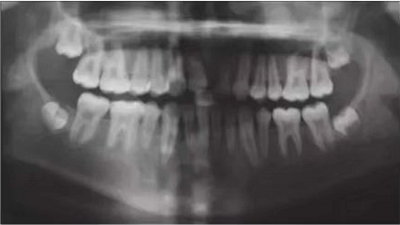

6個月后,移植牙的根尖片顯示治療期間沒有出現(xiàn)牙根吸收的影像?;颊邲]有出現(xiàn)不適,沒有發(fā)生牙齦炎。在23個月期間沒有進(jìn)行任何修復(fù)完成治療,達(dá)到I類關(guān)系(圖5和圖6)。

圖5. 正畸后影像學(xué)檢查